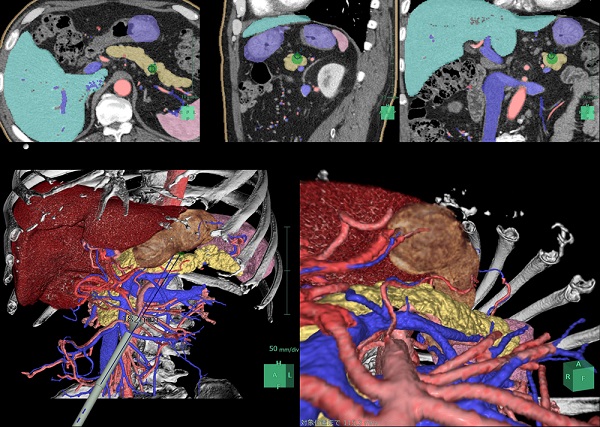

(1)膵臓自動抽出機能

肝胆膵外科・消化器外科の高いニーズに応え、抽出が難しいとされる膵臓のセグメンテーションが可能である。

従来は手動かつ熟練度に依存していたが、AI技術を活用し設計したセグメンテーション機能で、膵臓と周囲の血管や臓器との位置関係を明瞭に抽出することができる。これにより、肝胆膵領域の術前シミュレーションの幅が広がる。